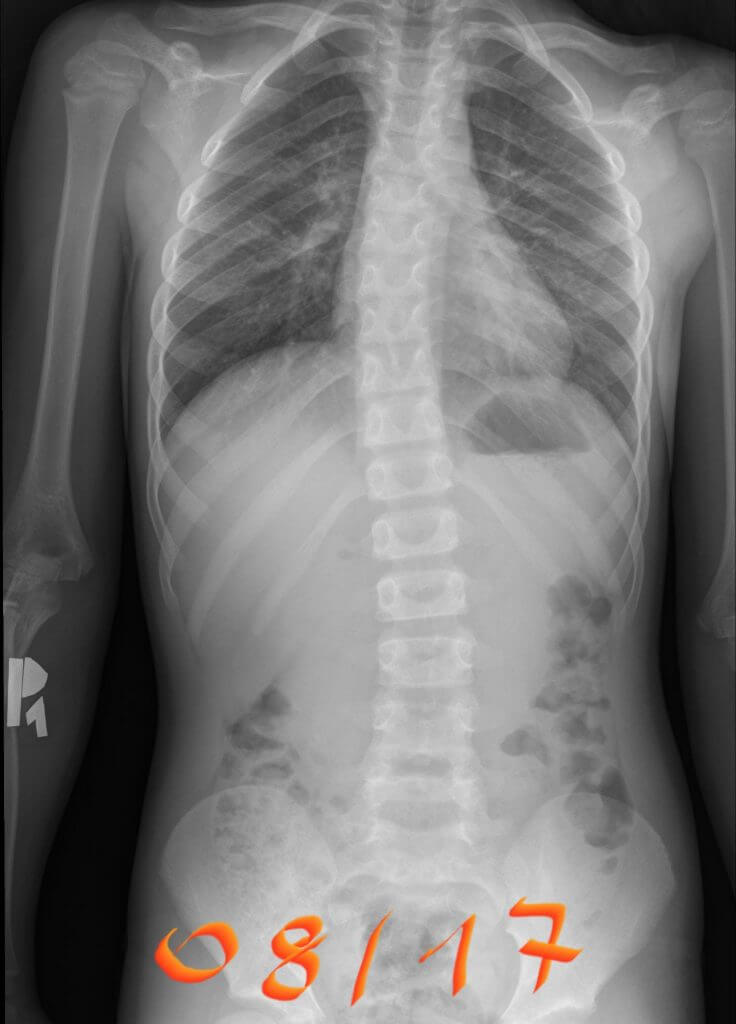

This patient was first seen by Scoliosisuk ltd in September 2017. She was recently seen in 2022 for a review and alterations of her Schroth Best Practice home program as scoliosis continues to need monitoring especially in large growth spurts . Her mum had spinal fusion and both parents are very supportive. She applies short bursts of exercise over 6-12 weeks, reviewing with low dose EOS X-rays and keeping herself super fit with her activities and sports. She has managed the condition without a brace since age 7 and now she is age 12 ! A great example of how to not only avoid surgery but also how to avoid bracing too ! Schroth Best practice can help reverse cobb angle if exercises are carried out well at home with support and the curves are less than 25 degrees. This matches the international guidelines for Scoliosis treatment criteria. Small curves need swift effective action and realistic Schroth programs rather than intensive overwhelming courses of physiotherapy.

‘A young small juvenile curve – uses Schroth Best Practice in short bursts and maintains her activities – avoids not only surgery but also bracing ! From age 7 to age 12!’